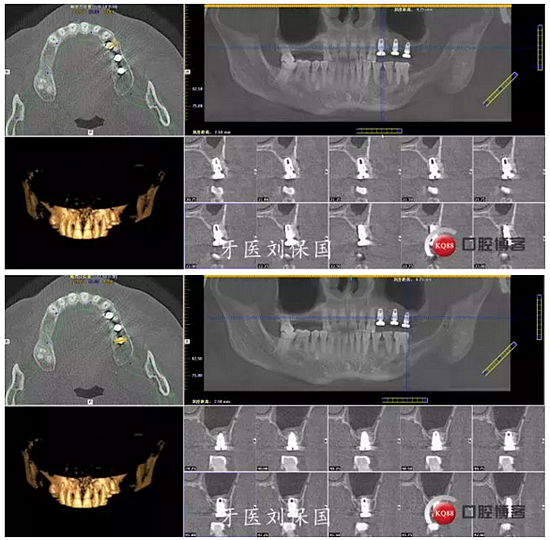

3.術(shù)后CT: